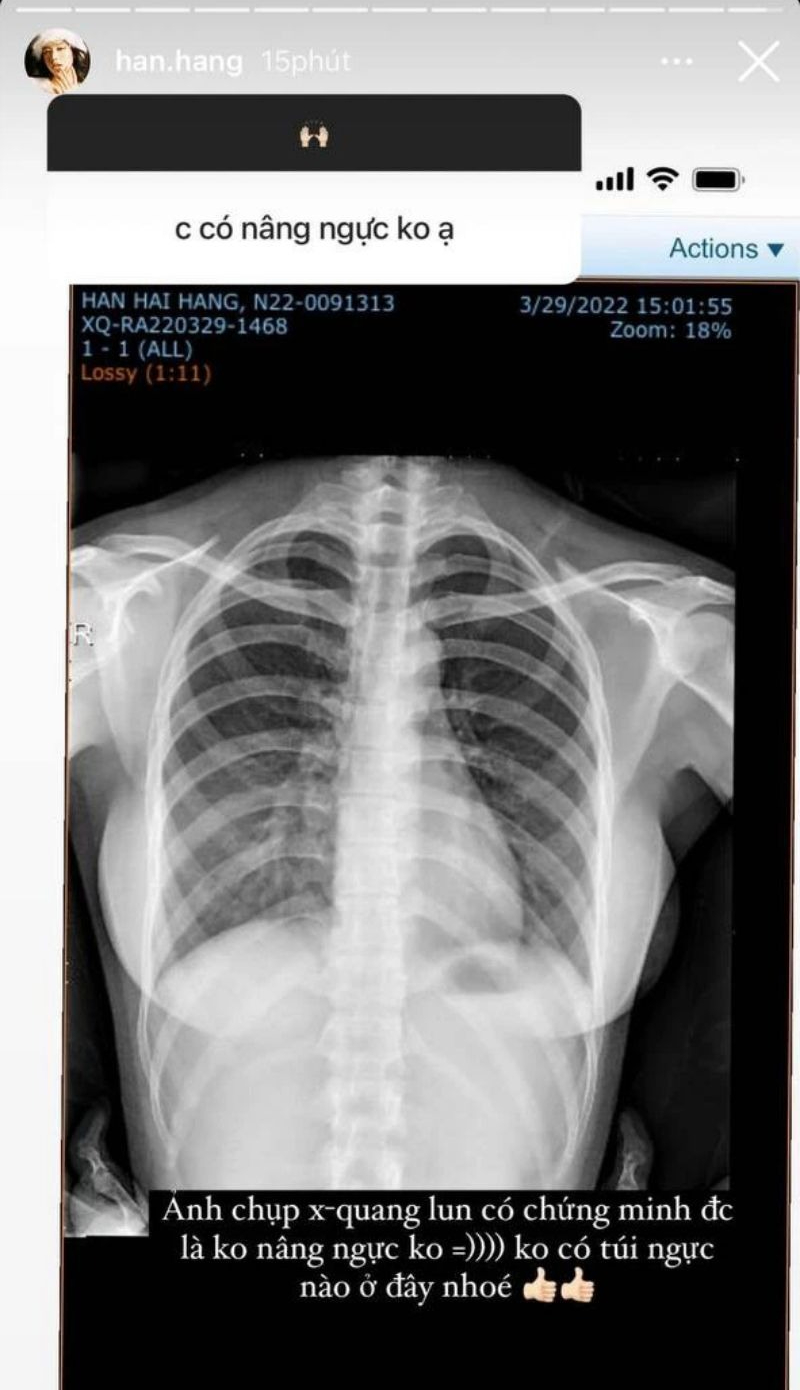

Năm 2022, trở lại MXH sau 2 năm ở ẩn, Hàn Hằng vẫn miệt mài chứng minh vòng 1 của mình không chỉnh sửa. Lần này cô tung hình chụp X-quang, khẳng định “không có túi ngực nào ở đây”.